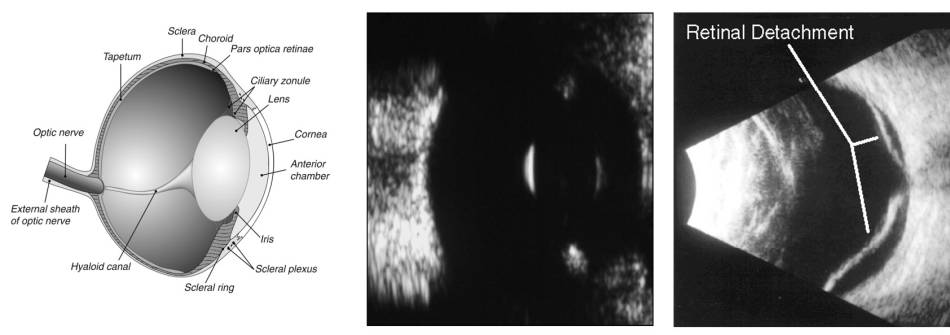

Augenultraschall

Technik

- Schallköpfe mit 20-100 Mhz

- Schall durch Kornea (am besten) oder durch Augenlider

- Kornea nur mit Abstand zum Schallkopf zu sehen

Befunde

- Vordere Augenkammer

- normal anechogen

- Hyphäma, Fibrin oder Hypopyon: feine Linien oder Cluster zu sehen

- bei Blutkoagula und festem Fibrin sind Massen erkennbar

- Iris und Ziliarkörper

- Tumore: Masse gesehen – sonst nicht zu sehen

- Linse

- Linse normal anechogen und die Linsenkapsel mit starker Echogenität

- Katarakt oder Nukleussklerose: in der Linse eine höhere Echogenität feststellbar

- Linsenluxation: leicht erkennbar

- Glaskörper

- normal klar und anechogen

- Blutungen, Entzündungen, Degeneration, Neoplasie: Verdichtungen

- Retina, Choroidea, Sklera

- normal: zusammen als stark hyperreflektive Grenze zu sehen

- Netzhautablösung: komplette Ablösung à Mövenflügeln

- Orbita

- Tumore, Entzündungen als hypoechogene Masse, welche zu Exophthalmus führt